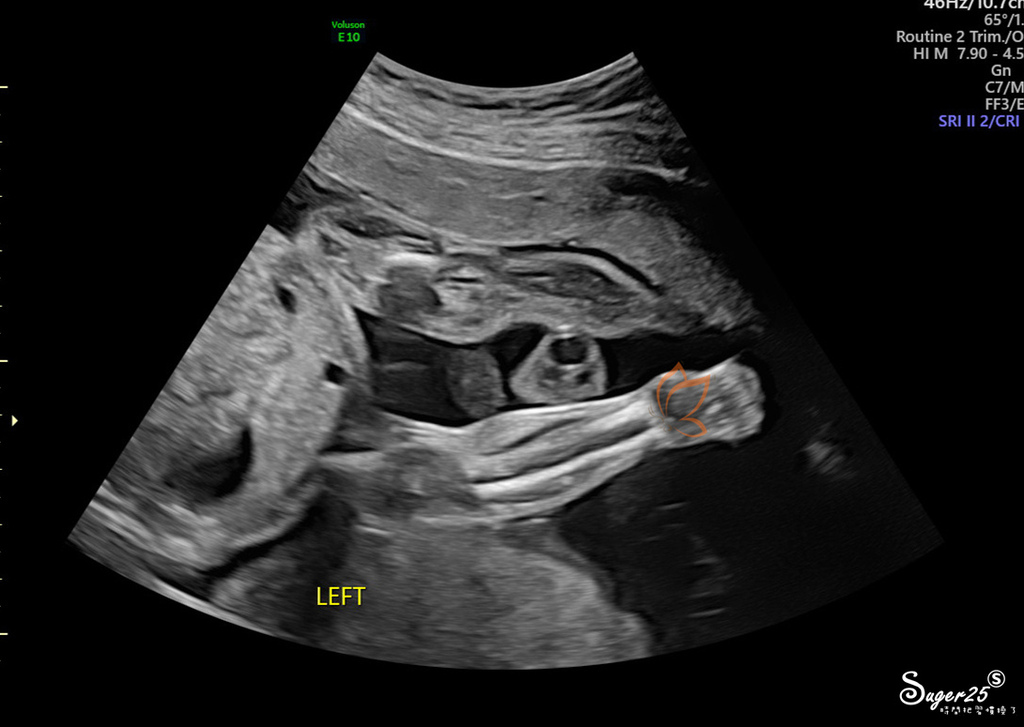

手臂

大腿